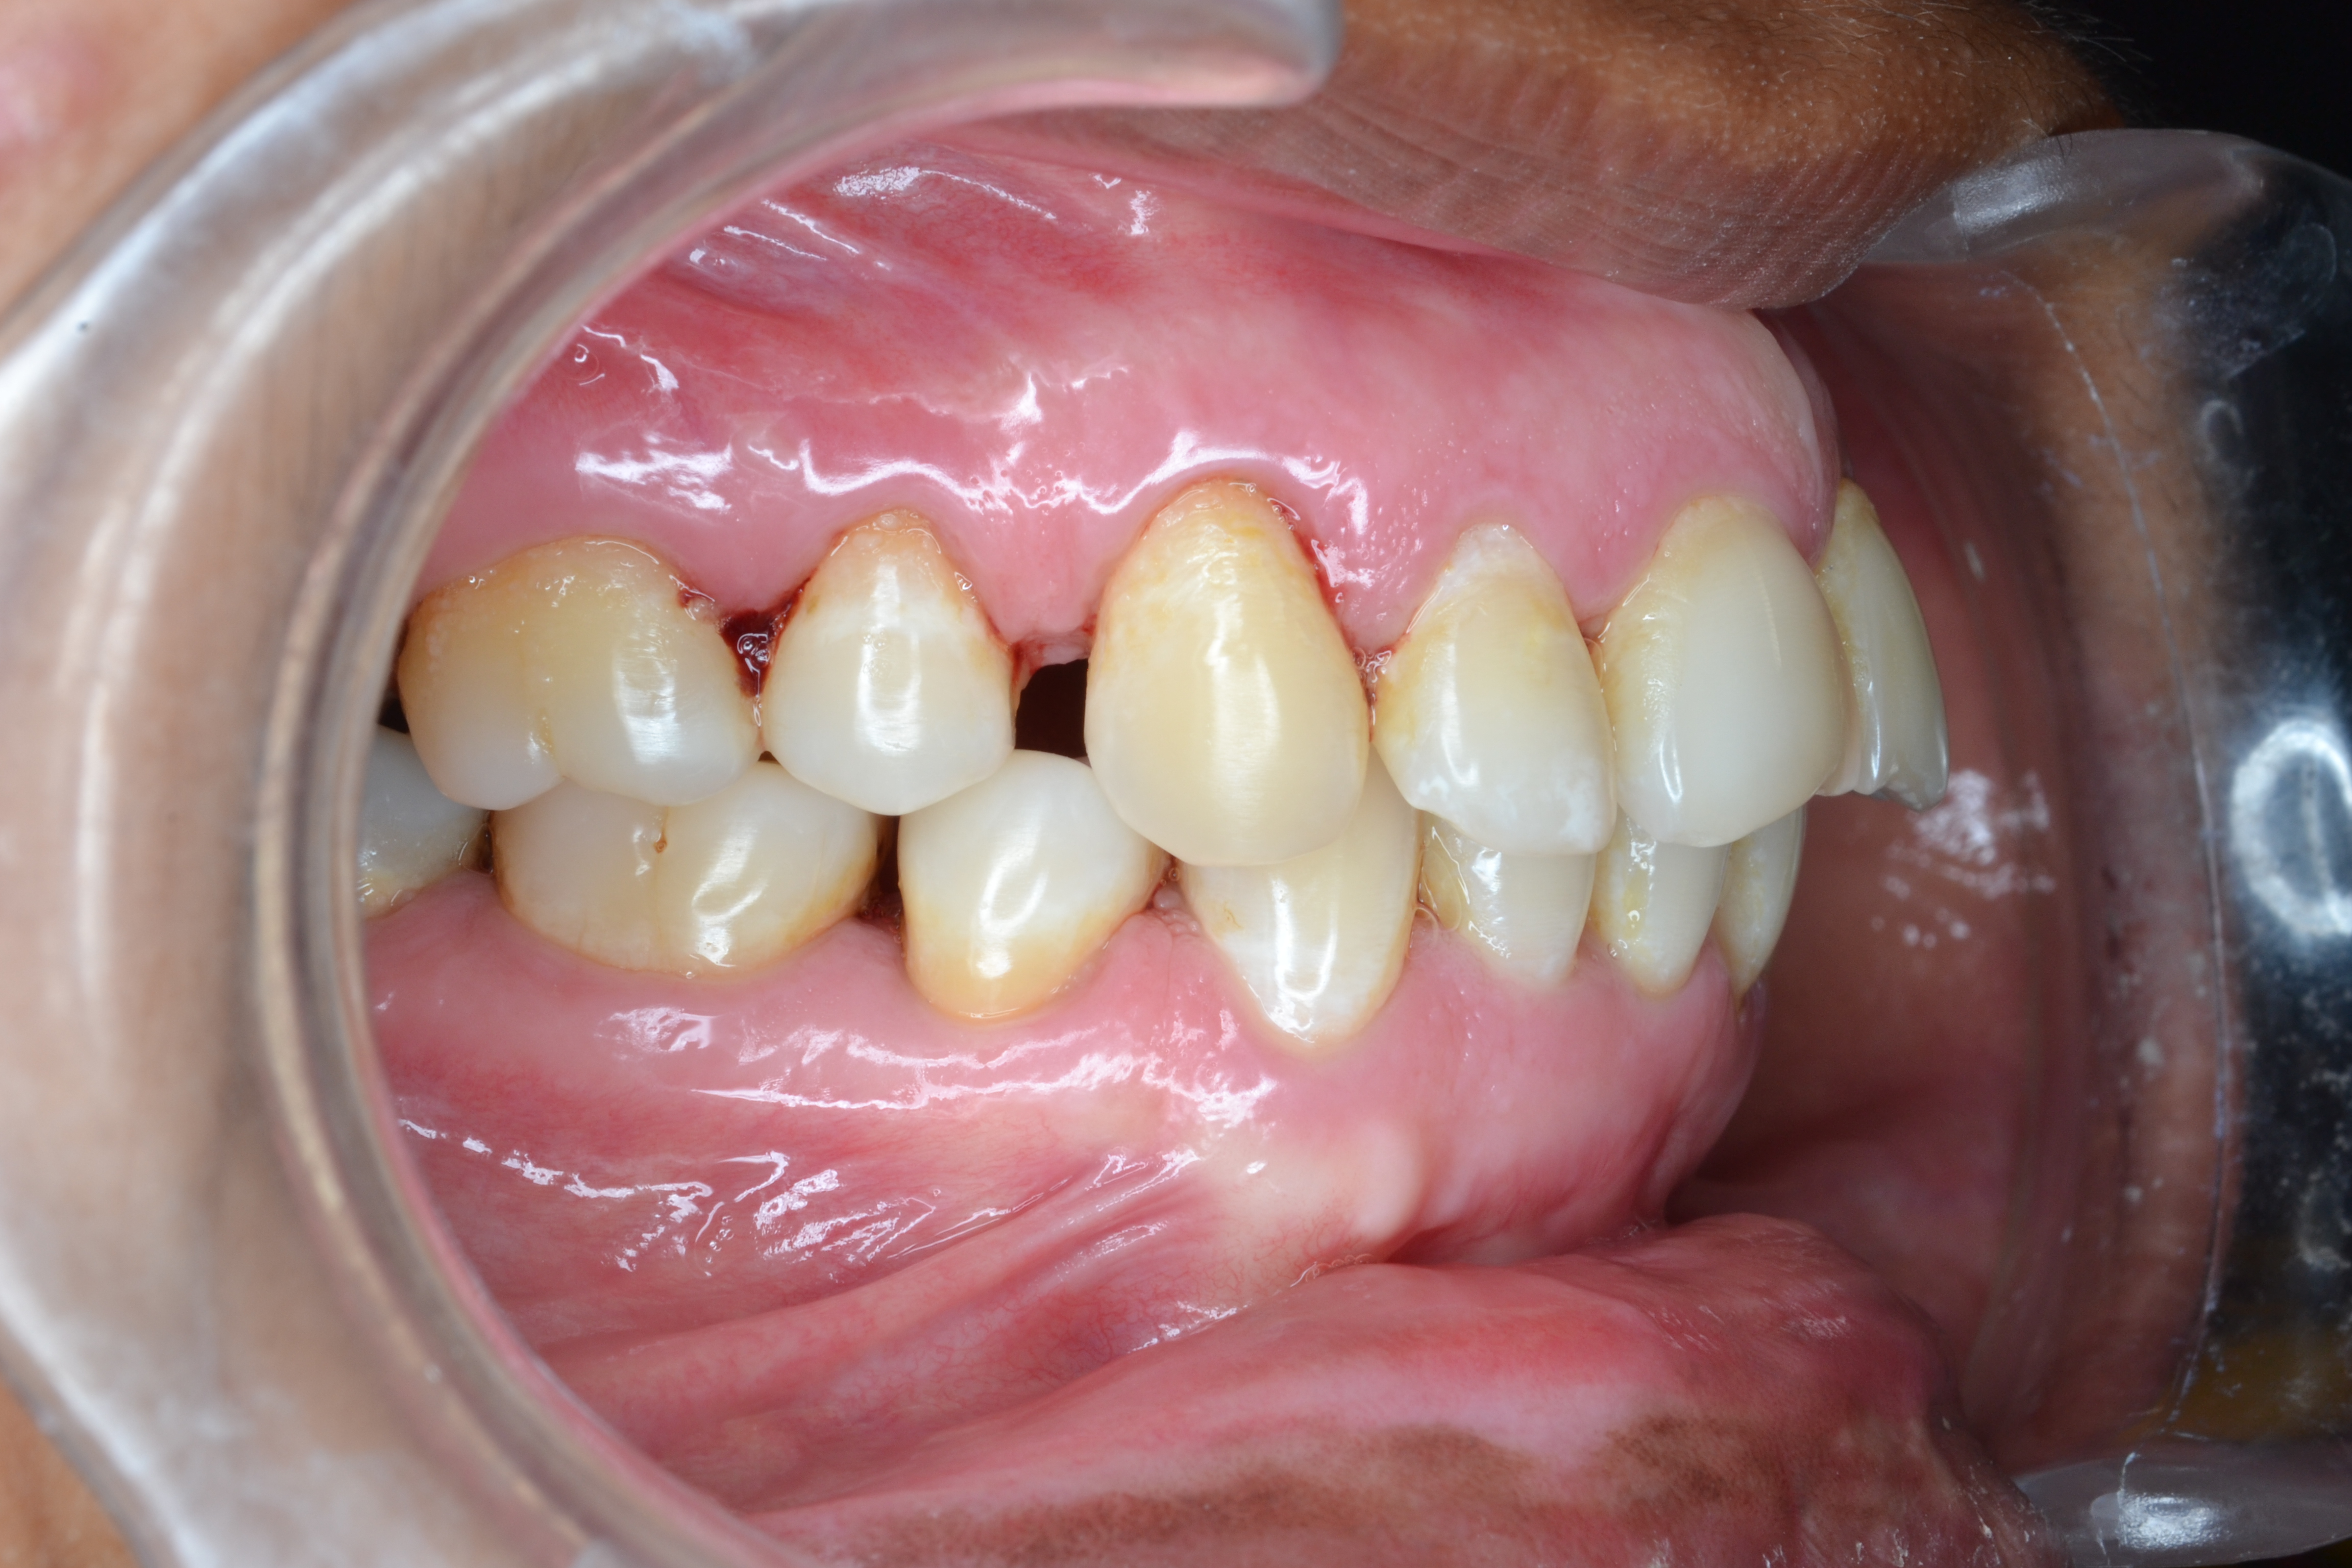

Sairam dental care located in Dharmapuri, with Leading Dentist In Oddapatti, is the Dental Hospital with exclusive root canal, Braces & Invisalign center. Led by renowned Drs Raghuraaman ( Periodontist) and Nivetha Raghuraaman ( Orthodontist) Sairam dental care offers gum treatment with expertise in laser, root canal treatment and digital smile correction with advanced technology aim to focus on aesthetics, comfort and precision. The clinic also specializes in Invisalign treatment, digital smile makeover, laser gum care, dental implants, root canal therapy, extractions and full-mouth rehabilitation blending compassionate care and clinical excellence.